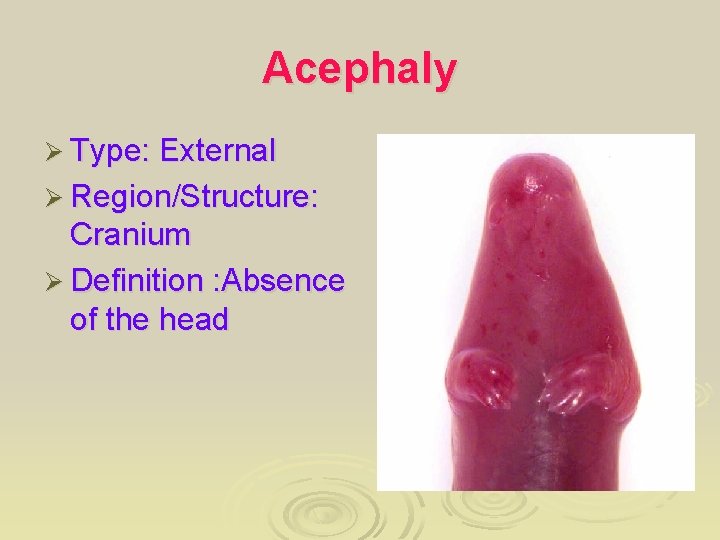

Acephaly Ø Type: External Ø Region/Structure: Cranium Ø Definition : Absence of the head